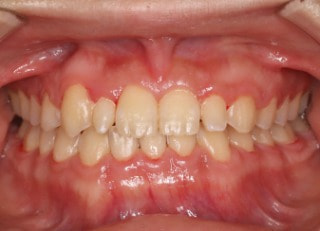

症例紹介

上顎2番矮小歯右下2番先天欠如

解説:下顎前突上顎劣勢長傾向で、上顎両側2番が矮小歯、右下2番先天欠如症例なので、上下前歯の幅径の比率を調節する必要があるケースです。(ご本人のご都合で治療中に来院できない期間がありました)

治療前